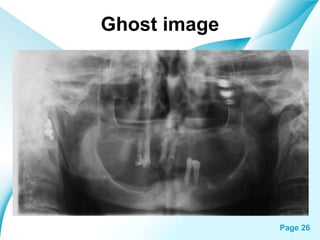

Ghost image